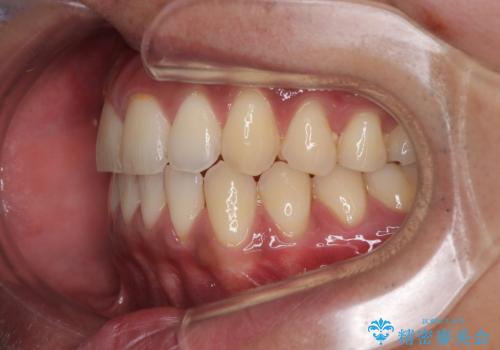

診察したところ、上下顎前歯部に軽度の叢生(ガタつき)が認められます。

目立たない装置を希望されたのでインビザライン ライトパッケージで治療を行うことになりました。